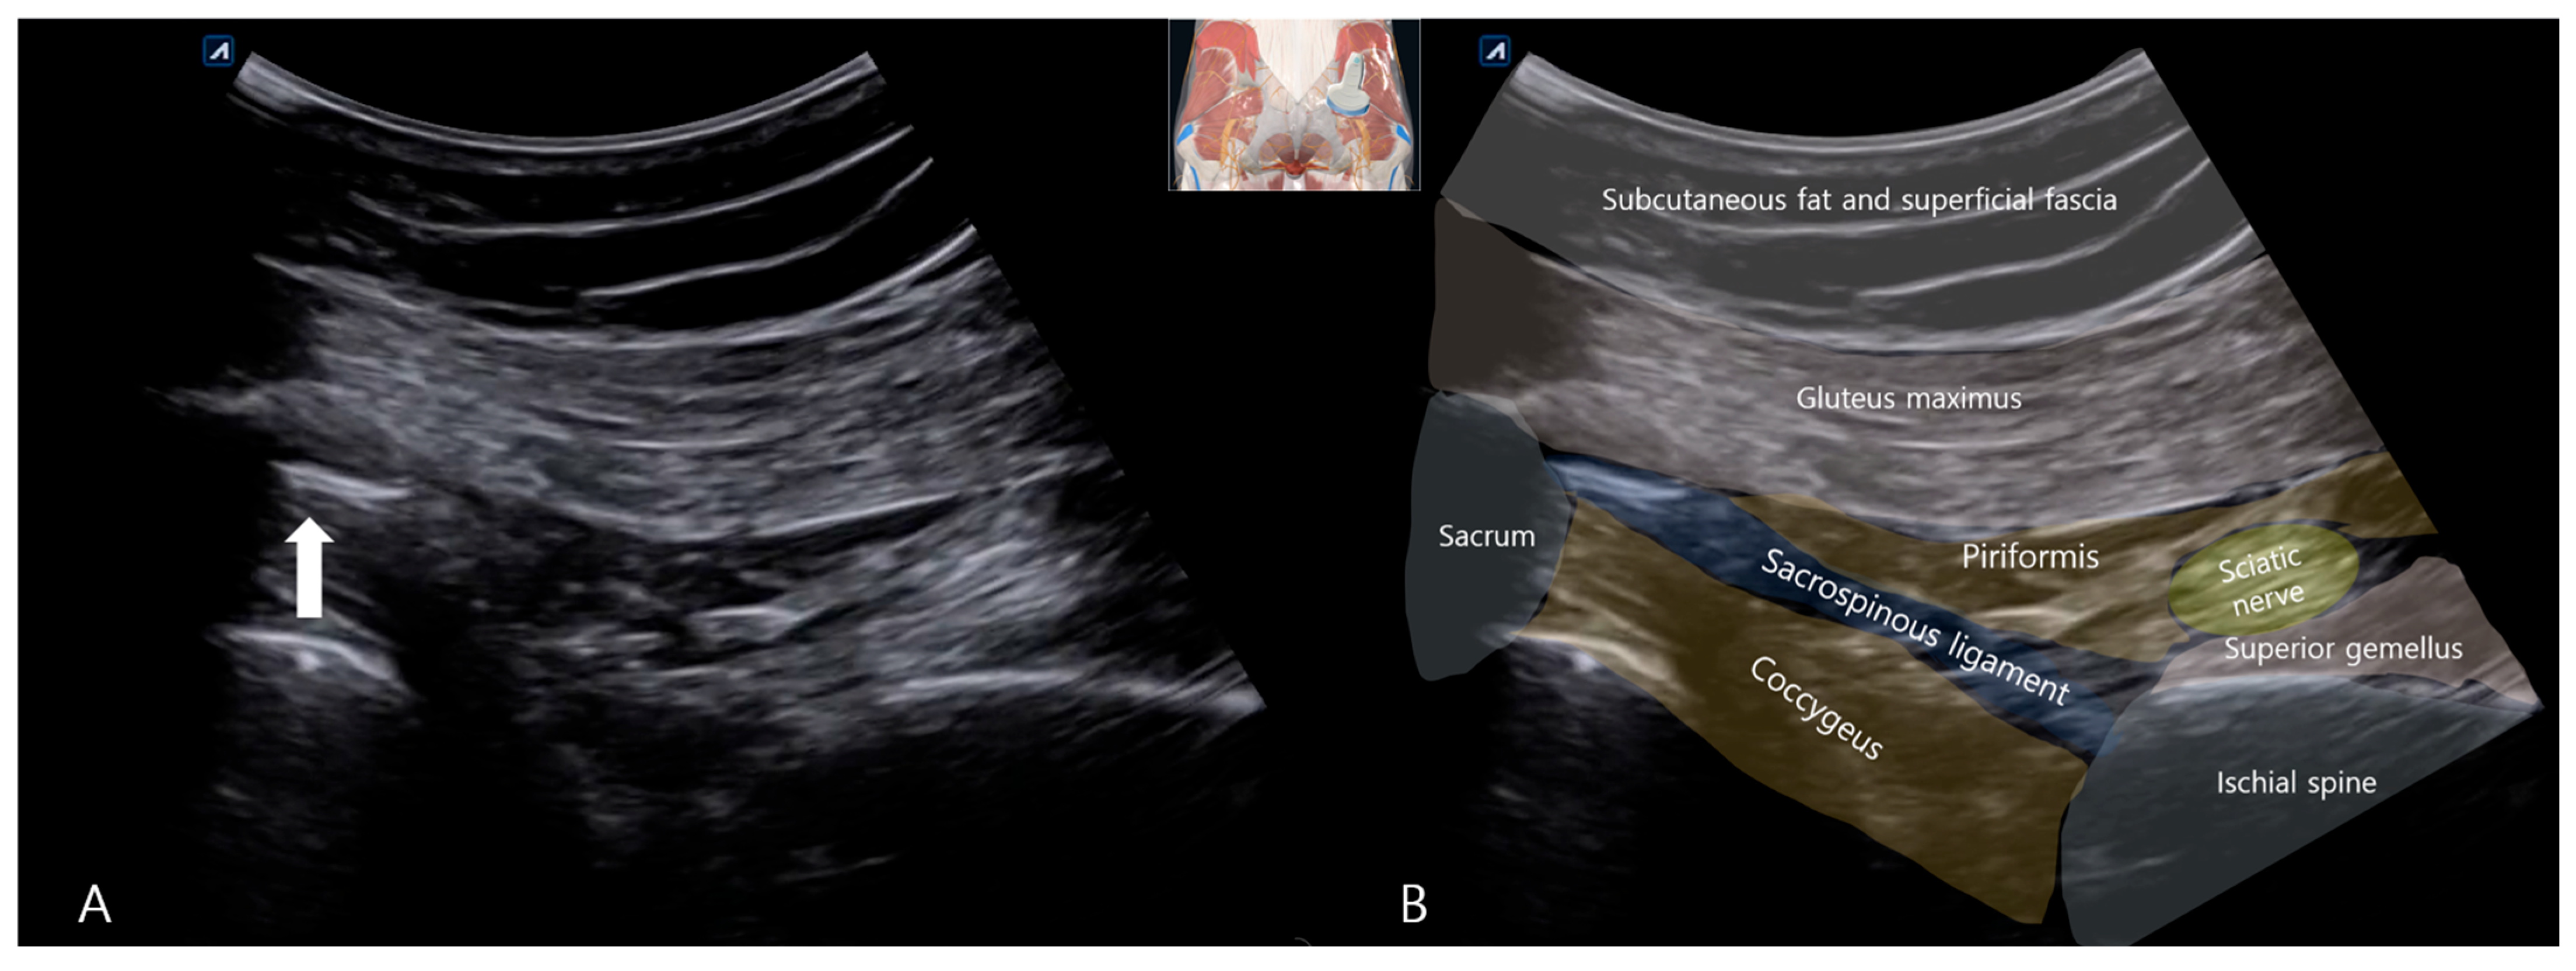

To investigate further and rule out bony pathology, plain radiographs of the pelvis (anteroposterior (AP) and oblique views) and lumbar spine (AP and lateral views) were obtained using a standard radiographic unit (Siemens Ysio Max, Erlangen, Germany). Images were acquired with the patient standing for pelvic views (AP: 70 kVp, 25 mAs; Oblique: 75 kVp, 30 mAs) and supine for lumbar views (AP: 75 kVp, 30 mAs; Lateral: 85 kVp, 40 mAs). The AP pelvis radiograph revealed a well-defined, ovoid calcific density adjacent to the left inferolateral margin of the sacrum, precisely at the expected anatomical location of the SSL’s sacral attachment (Figure 1A). No significant hip joint arthropathy was noted, though a small, unrelated calcification was incidentally noted at the right greater trochanter, likely representing a benign enthesopathy or trochanteric calcific tendinitis. The lateral lumbar view confirmed mild disk space narrowing at L5-S1 (Figure 1B), consistent with early degenerative changes, but no spondylolisthesis, dynamic instability, or other significant findings that could account for her severe symptoms.

Figure 1. Lumbar AP, Lateral X-ray (A) Anteroposterior radiograph of the pelvis showing a well-defined calcific density at the left inferolateral sacrum (white arrow), corresponding to the anatomical location of the sacrospinous ligament. (B) Lateral lumbar spine radiograph demonstrating narrowing of the L5–S1 intervertebral disk space (white arrow), consistent with mild degenerative changes.